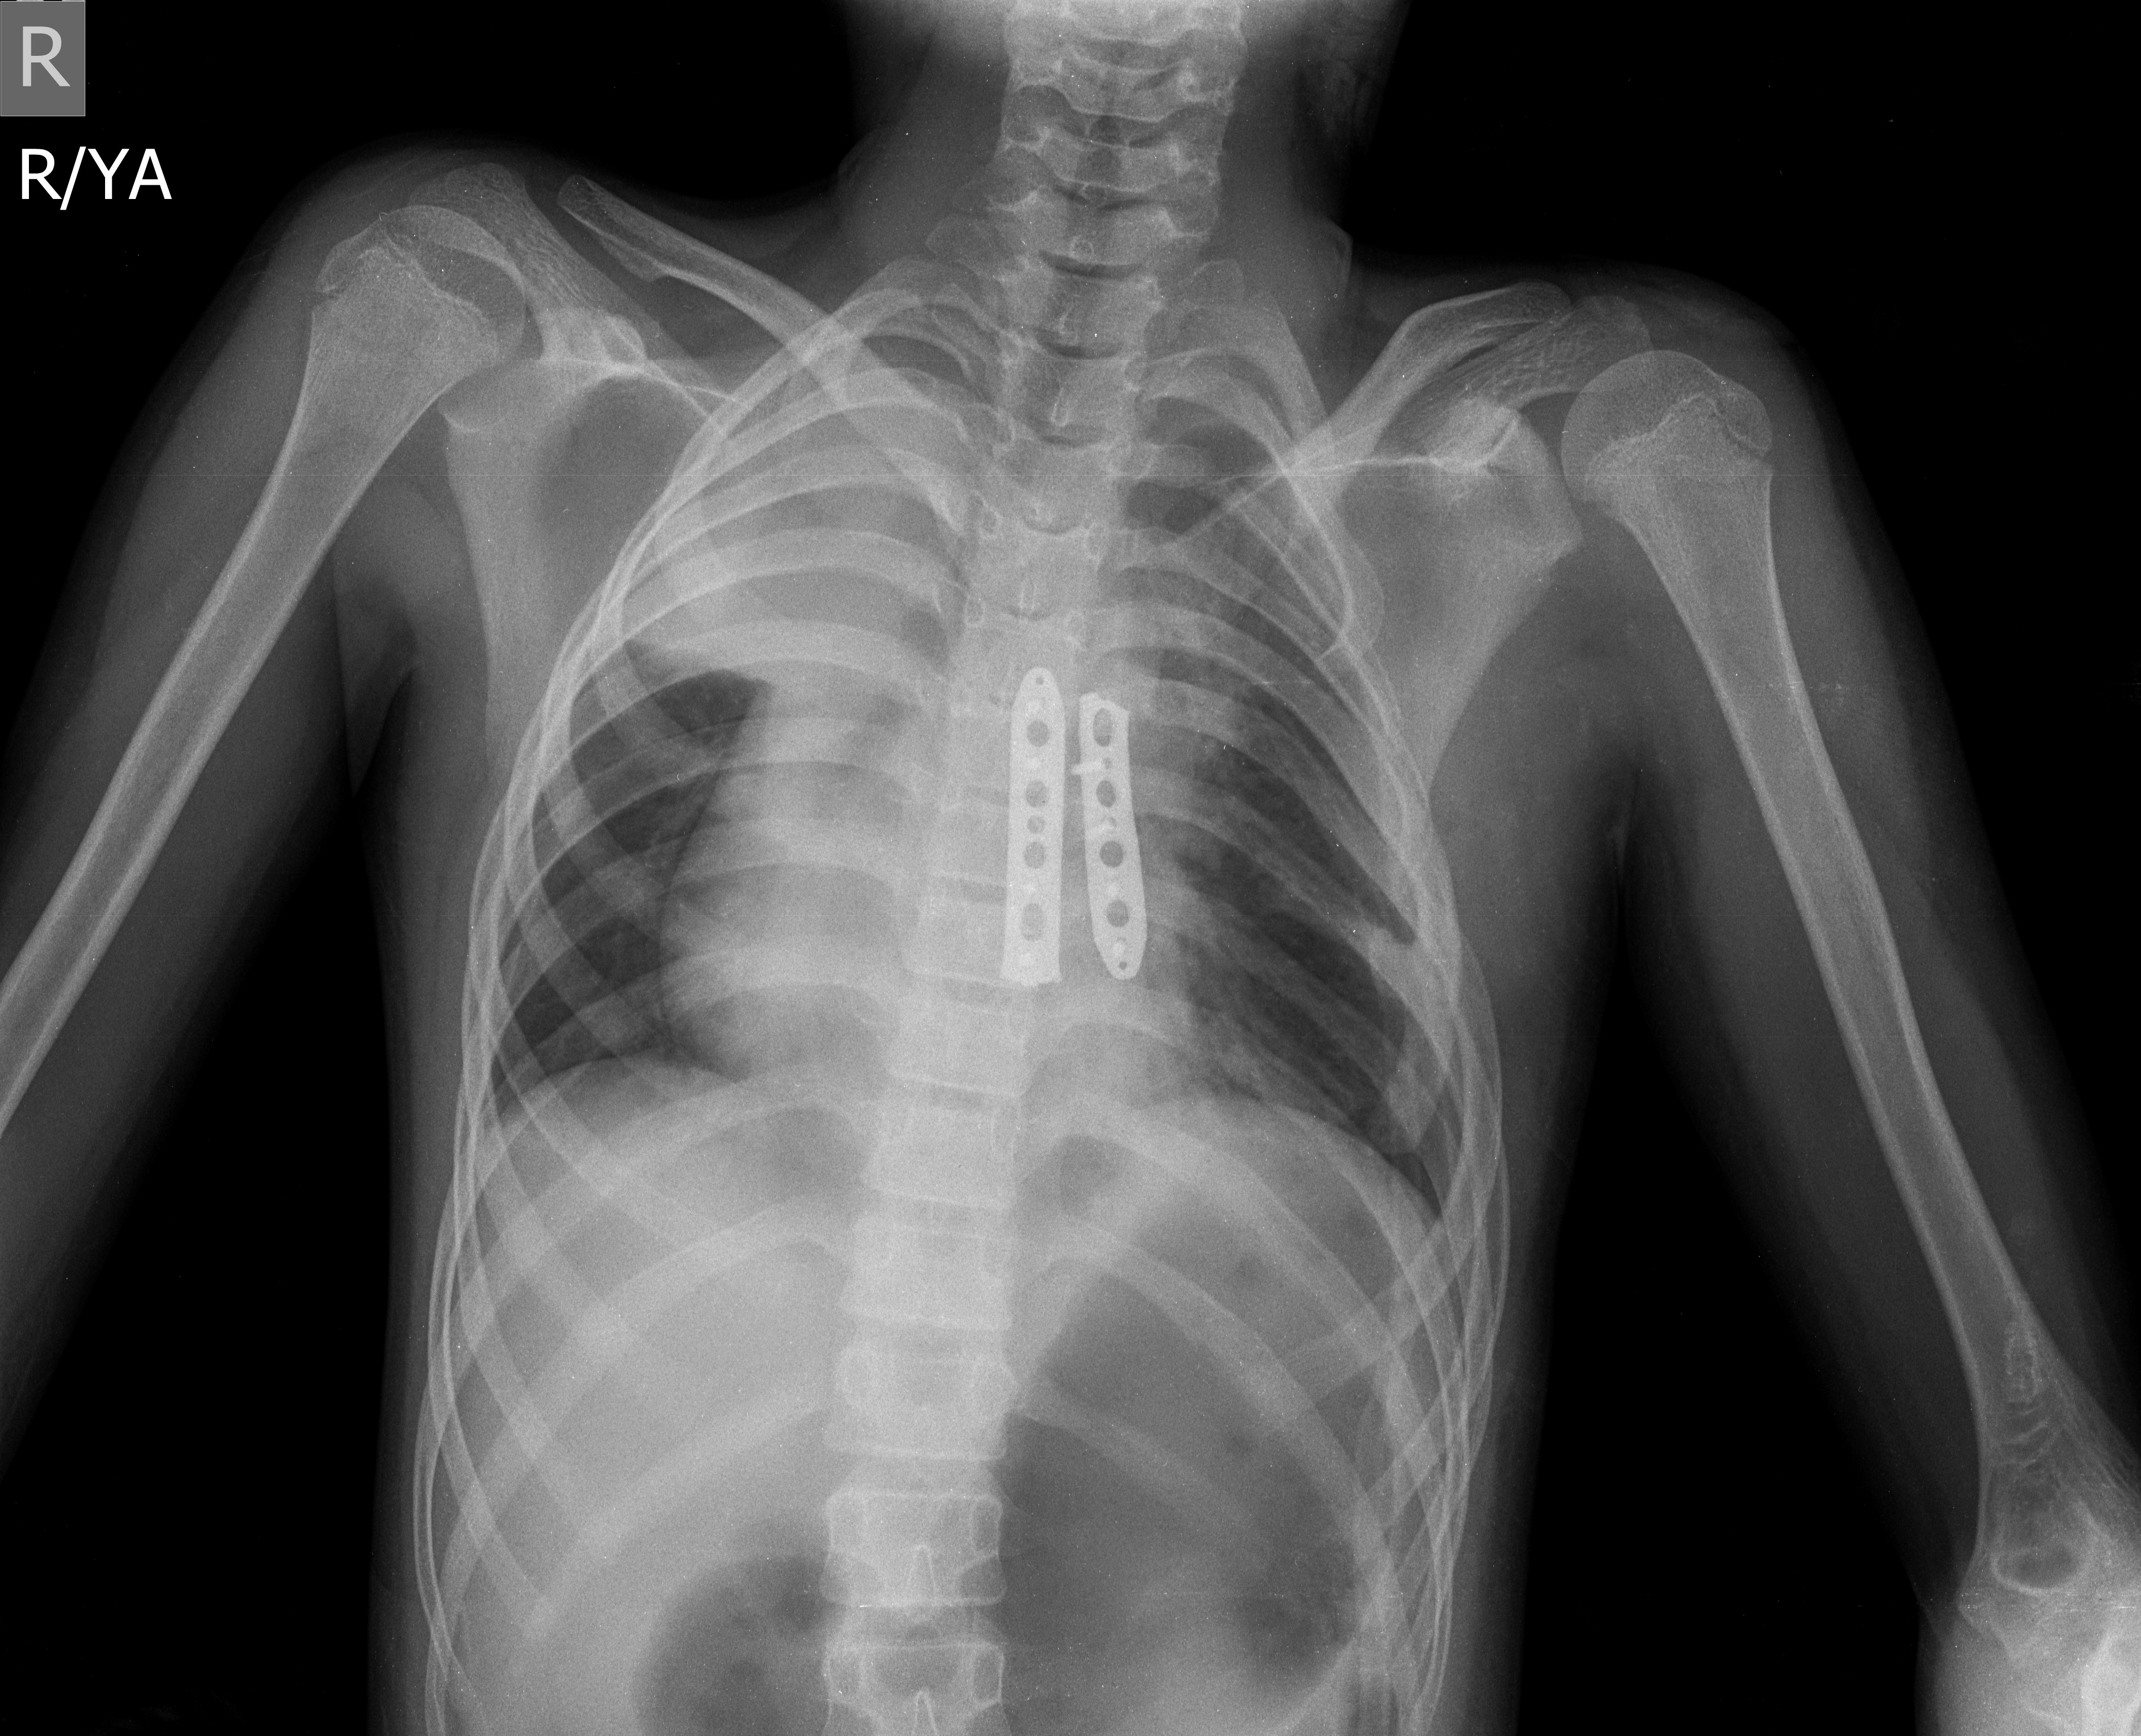

Девочка 10 лет с синдромом Поланда, 2-е сутки после операции - торакопластика, плевральные полости не вскрывались. Типичная ли здесь дестракардия? Какого генеза ателектаз, артефакт имитирующий...

Тип: Клиническое наблюдение

Область: Грудная клетка и верхние дыхательные пути

Модальность: Rg

Дата: 14.09.2018 - 09:01